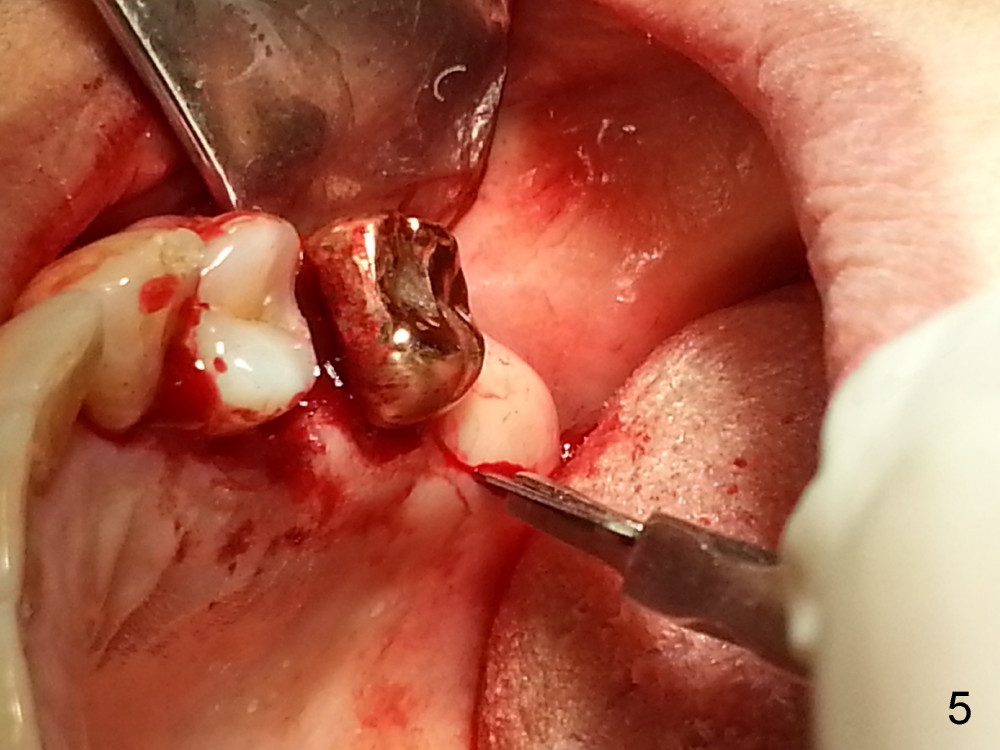

The tooth #13 appears to be affected by periodontits and occlusal trauma (Fig.1*). After using a periotome (Fig.2), the tooth is extracted (Fig.3). The buccal flap is raised (Fig.4). Gingival graft is to be harvested from the site of #15 (Fig.5). The tissue is elevated buccally (Fig.6) and separated (Fig.7). The donor site is covered by a collagen membrane (Fig.8*). A diamond bur is used to induce bleeding from the socket (Fig.9*). Osteotomy is initiated (Fig.10) and enlarged (Fig.11,12). A tapered implant is being placed (Fig.13-15) following internal sinus lift (Fig.16,17). The implant is placed subcrestally, followed by bone graft (Fig.18), soft tissue graft (Fig.19), and suturing (Fig.20 <, Fig.21).